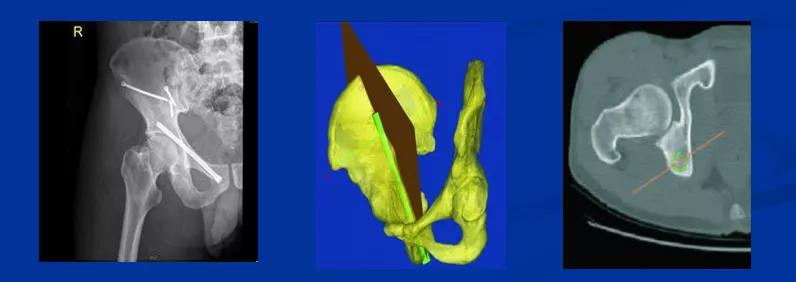

微创治疗的方法1、闭合复位微创前柱螺钉固定2、微创复位后柱螺钉固定3、王钢的设计:螺钉导向器

微创复位前路插板固定(本报道)后入路:K-L入路解决后柱、后壁/柱骨骨折移位并用重建板固定前入路:通过间接复位前柱或前壁插板固定

插板1、切口2、通道及方向、技巧3、固定螺钉的顺序4、插板注意事项:曲髋、死亡动脉

10、沿髂耻嵴插板,在耻骨上支用2枚螺钉固定,维持前柱,前壁解剖序列连续性,再髂骨上固定另一枚螺钉,起到断端加压作用。